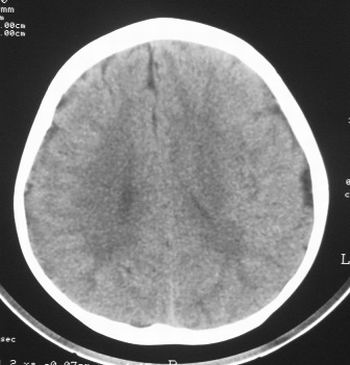

患儿,男,8岁,外伤2小时,无恶心、呕吐,四肢活动正常。既往无任何不适,智力发育正常。

典型的左中颅窝蛛网膜囊肿。

典型的左中颅窝蛛网膜囊肿。最常见的发病部位,张力比较高,相应颅板受压变薄。赶紧治疗,脑组织的功能可能部分恢复。